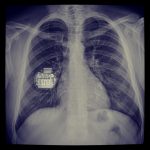

Οι βηματοδότες αποτελούνται από τη γεννήτρια (συσκευή), που διαθέτει μπαταρία καθώς και ένα ηλεκτρικό κύκλωμα το οποίο επεξεργάζεται τις πληροφορίες που λαμβάνει από το φυσικό ηλεκτρικό κύκλωμα της καρδιάς και, ανάλογα με τις ρυθμίσεις που διαθέτει, παρεμβαίνει ή ελέγχει την ηλεκτρική δραστηριότητά της και τα ηλεκτρόδια (καλώδια), που συνδέουν τη συσκευή με το εσωτερικό της καρδιάς και είναι από ένα έως τρία.

Η τοποθέτηση (εμφύτευση) του βηματοδότη γίνεται με τοπική αναισθησία κάτω από το δέρμα του ασθενούς σε θήκη που ο γιατρός θα διαμορφώσει στον θώρακά του. Τα καλώδια τοποθετούνται μέσα από καθετηριασμό φλέβας στο εσωτερικό της καρδιάς και με το μεταλλικό τους άκρο στερεώνονται μόνιμα. Η τοποθέτηση των καλωδίων αποτελεί και το πιο ευαίσθητο και χρονοβόρο τμήμα της εμφύτευσης του βηματοδότη.